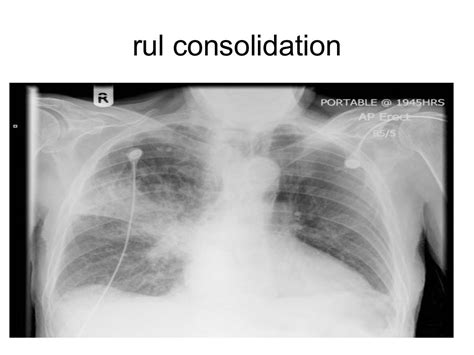

The consolidation of lung refers to a condition where the lung tissue becomes solid and firm due to the accumulation of fluid, cells, or other substances, replacing the normal air-filled spaces. This can be caused by a variety of factors, including infections, inflammation, and injury. In medical imaging, consolidation is often seen on chest X-rays or computed tomography (CT) scans, where it appears as a homogeneous area of increased density. Understanding the causes, symptoms, and diagnosis of lung consolidation is crucial for effective management and treatment.

- Diagnosis of lung consolidation involves medical imaging, such as chest X-rays or CT scans, and laboratory tests, including blood cultures and sputum analysis.

The diagnosis of lung consolidation involves a combination of clinical evaluation, medical imaging, and laboratory tests. A physical examination and medical history can provide clues to the underlying cause, while chest X-rays and CT scans can help identify areas of consolidation. Laboratory tests, such as blood cultures and sputum analysis, can help identify the causative agent and guide treatment.